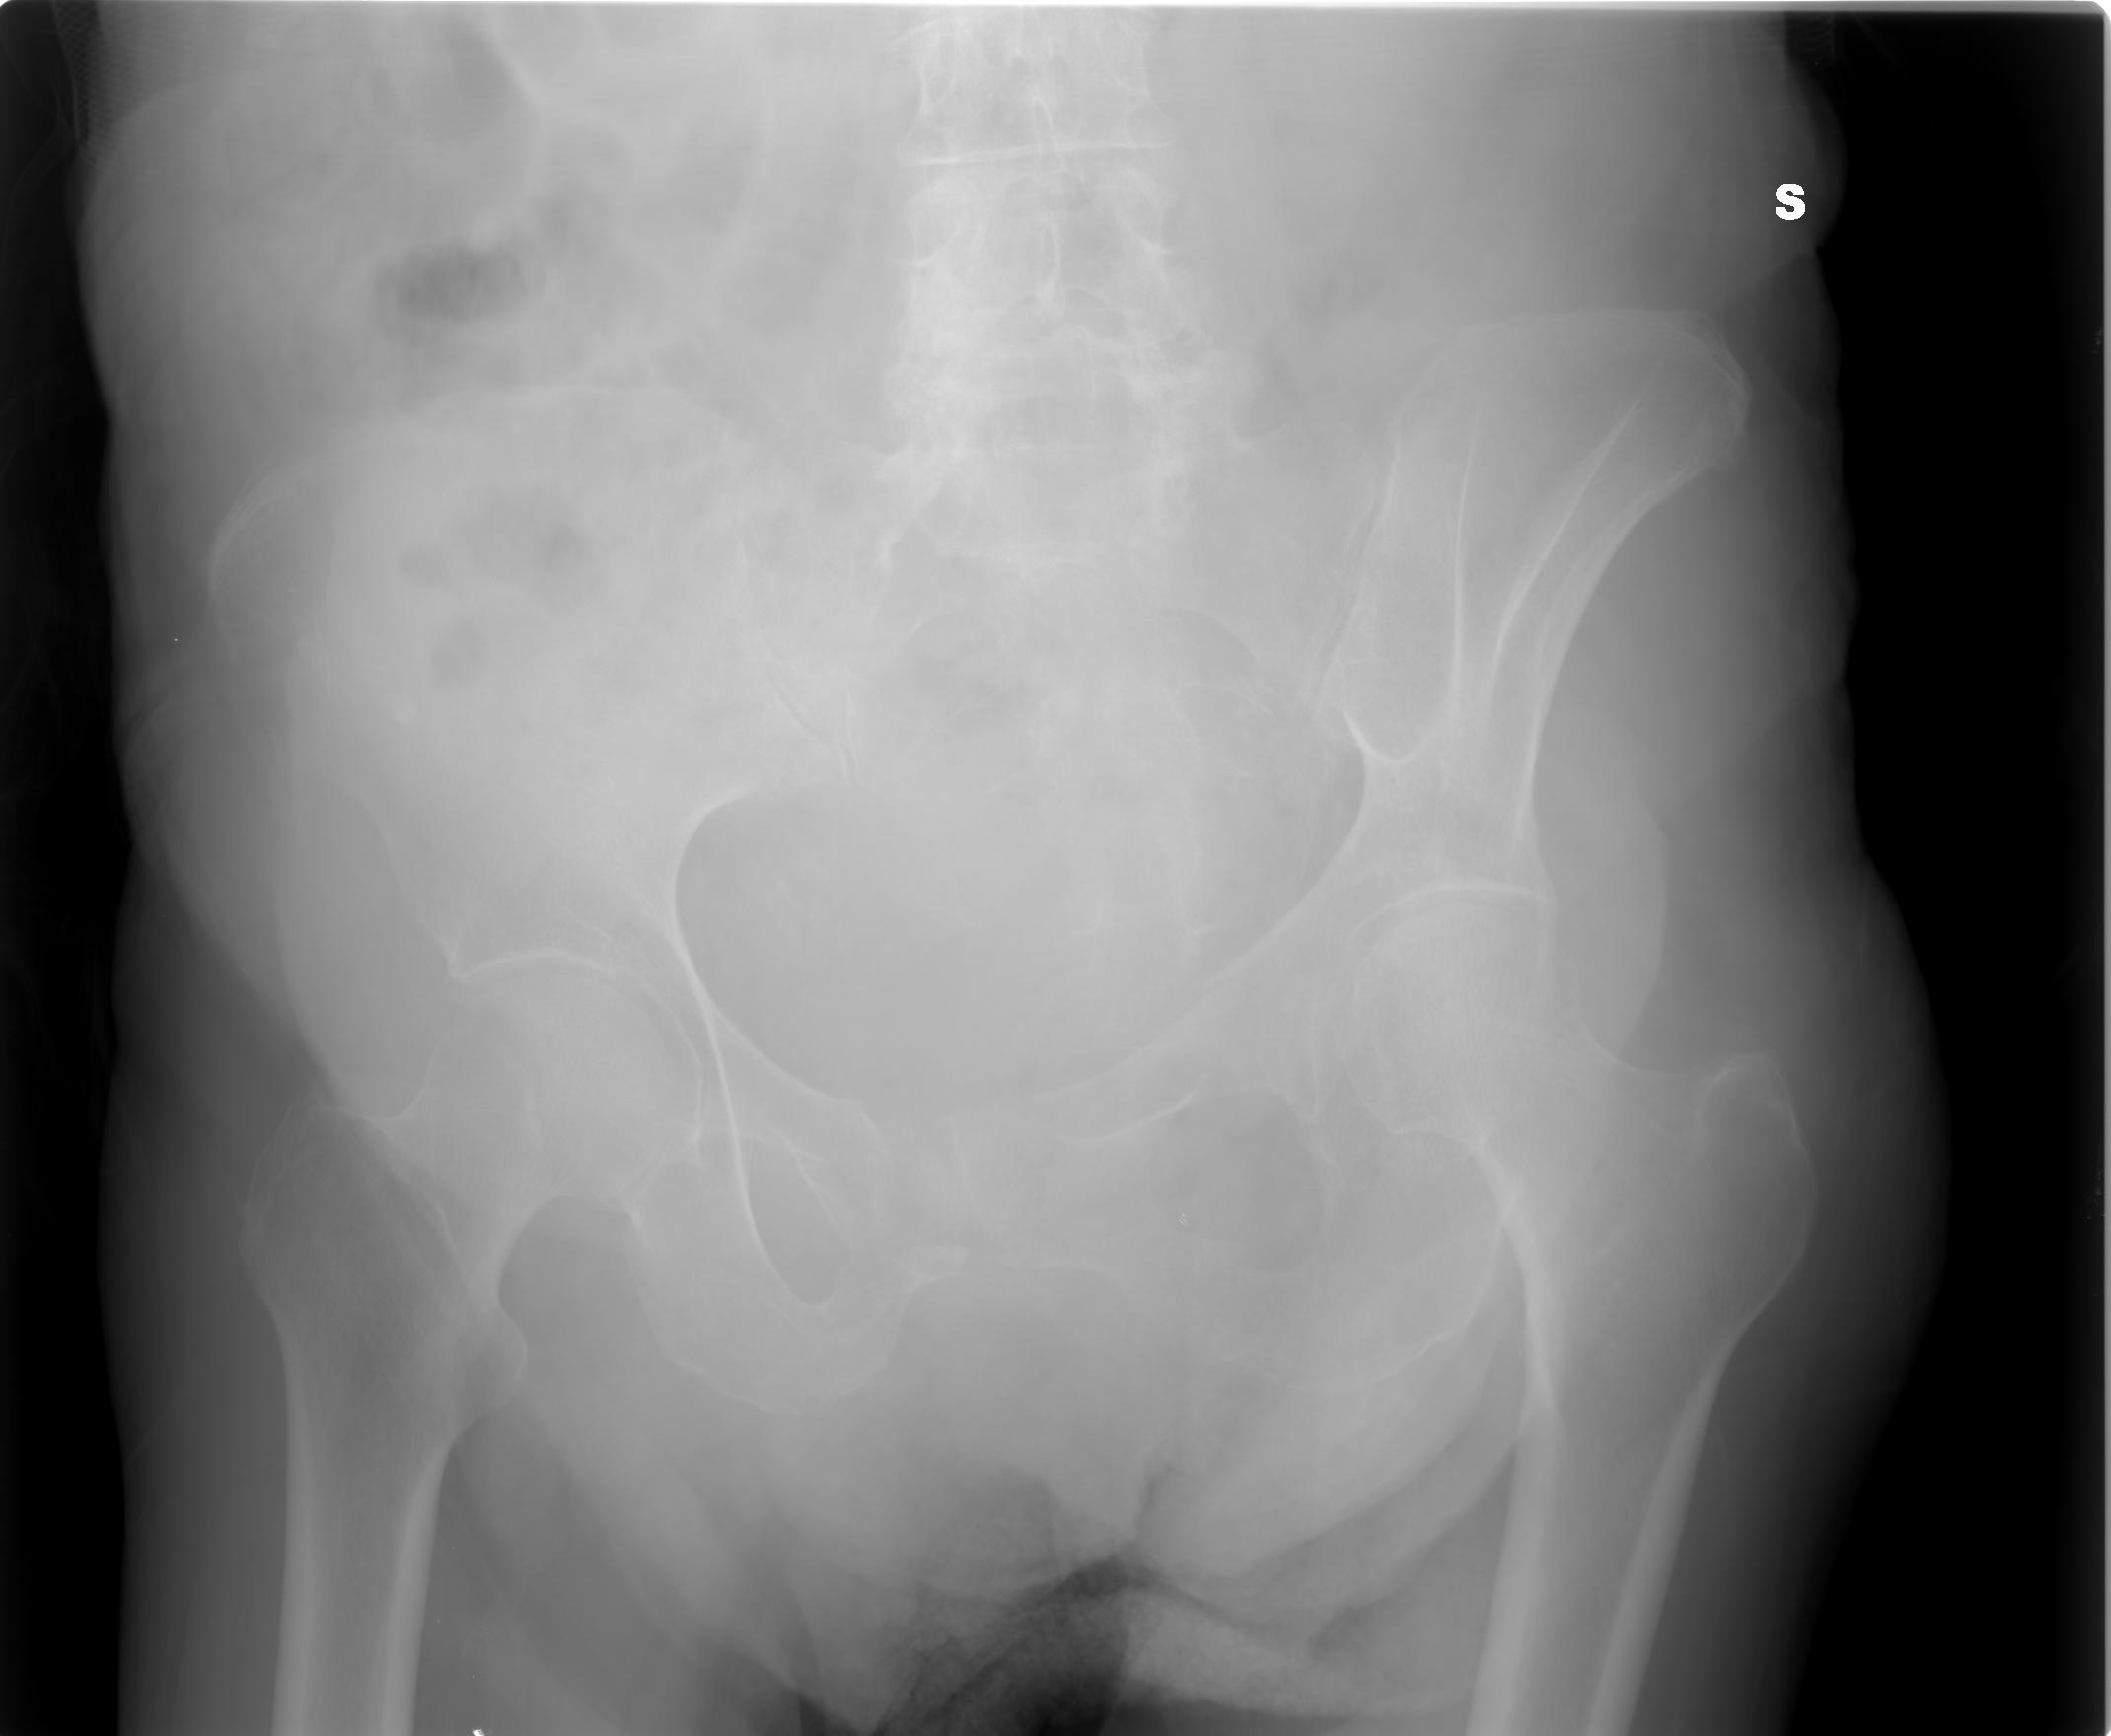

SALVE, ho ritirato un referto lastra per mia madre 80 anni e dice le seguenti parole: per quanto apprezzabile nel radiogramma a disposizione si osserva frattura composta della branca ile pubica sinistra .Sospetta frattura (o esiti fratturativi?) a carico dell branca ischio pubica omolaterale.

allego le lastre potete consigliarmi?